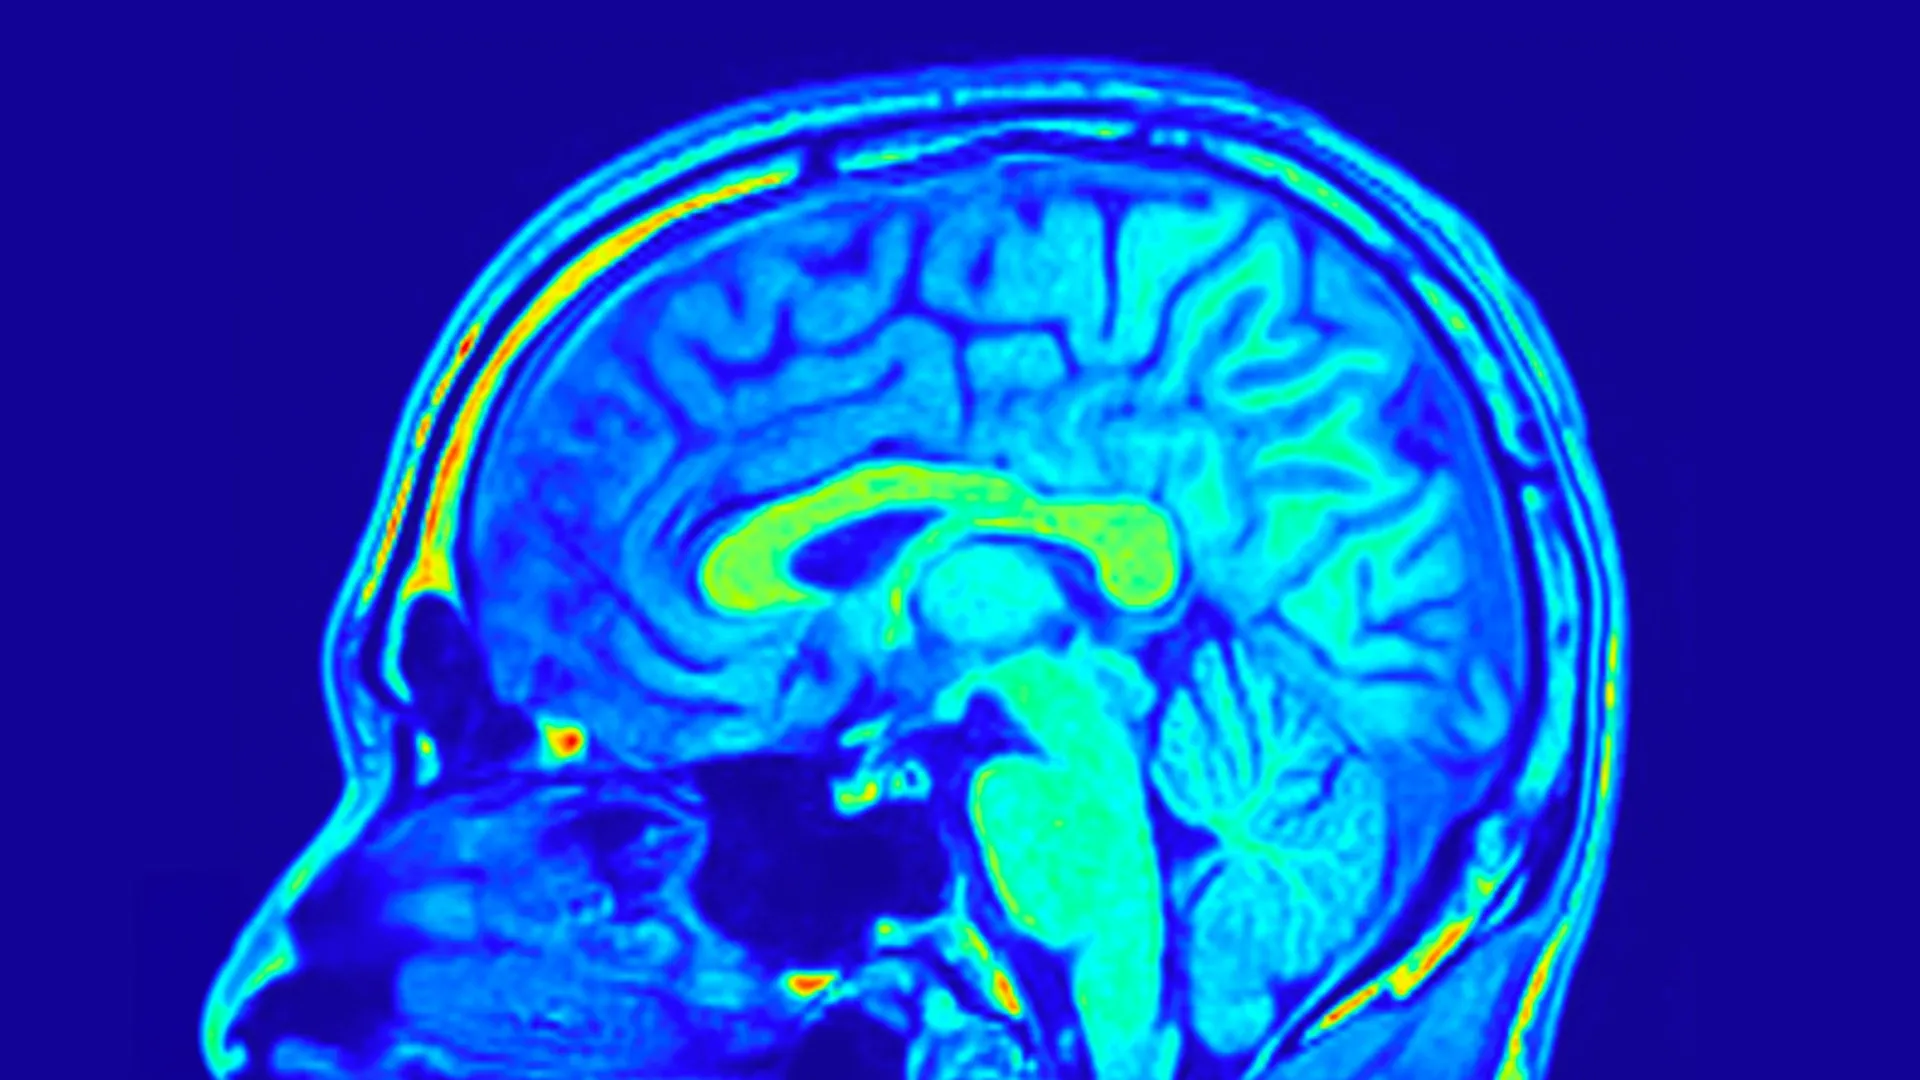

New scans and neurofeedback therapies reveal what trauma does to the brain -- and show veterans proof that recovery is real.

Brain scans may finally end the guesswork in depression treatment

Major depressive disorder (MDD) is a widespread and serious mental health condition that affects how people think, feel, and function in daily life.